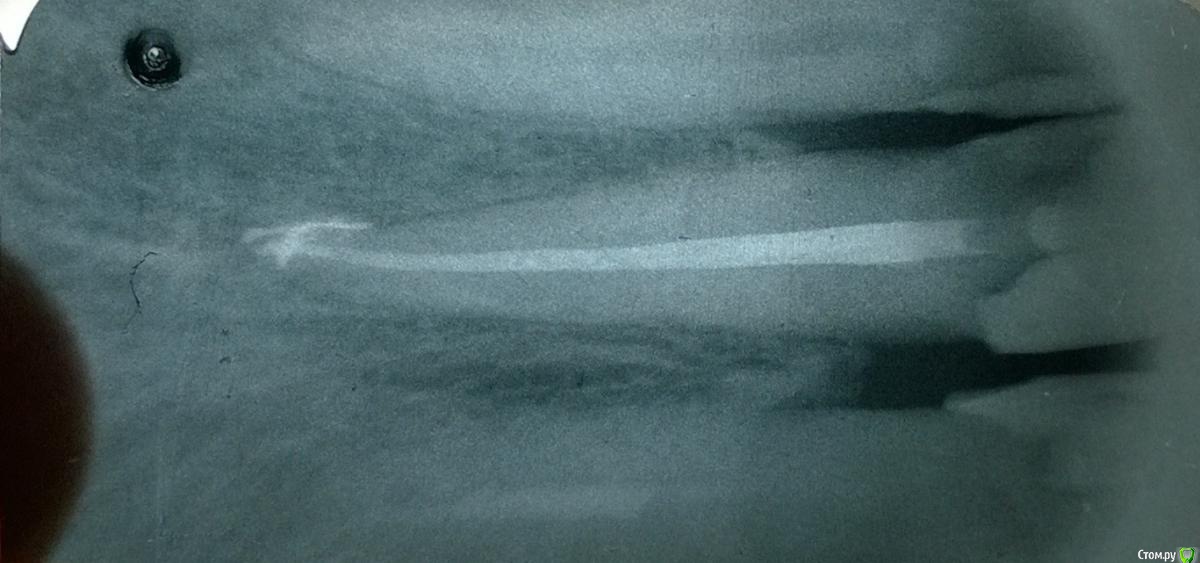

Arcus Опубликовано 6 декабря, 2014 Поделиться Опубликовано 6 декабря, 2014 В этом году закончил интернатуру, поэтому любая критика будет очень полезна Пациентка 58 лет пришла с обострением периодонтита зуба 11, перкуссия резко болезнена, был отек переходной складки, но инфильтрата я не пропальпировал (разрез по переходной складке сделал, но гнойного экссудата не получил , дренаж не ставил).Вот протокол по которому работал:1. Обезболивание2. Наложение коффердама3. Создание доступа (пригодилась эта статья, спасибо Kivilgar)4. Введение RC-prep и прохождение k-file 10 с апекслокатором до 0.0. Измерил линейкой и от этой длины отнял 3 мм, и начал обрабатывать канал на эту длину помощью Protaper S1, S2. Промыл гипохлоритом, подключил апекслокатор и прошел последние 3 мм К файлами 10,15,20,25 сделал рентгеновский снимок. По нему файл был на уровне рентгенологической верхушки, пришлось уменьшить рабочую длину еще на 0,5 мм.5. На полную рабочую длину обработал корневой канал Protaper S1, S2, F1, F2, потом у апекса дорабатывал K файлами NiTi 30,35,40. После каждого файла промывал канал гипохлоритом натрия и проводил рекапитуляцию 10 файлом.6. Медикаментозная обработка перед временным пломбированием. Гипохлорит натрия, высушил пинами, хлоргексидин 2% на 2 мин, высушил пинами, спирт 95%, высушил пинами. Ввел Metapaste, притрамбовал бумажным пином, ватка, временная повязка Кависил. (верхний зуб) Назначил найз по 1 таб 2 р в день, 5 дней и линкомицин 2 кап 3 раза в день 5 дней. (тут прошу совета, нужно ли назначать антибиотик при обострении периодонтита, когда имеется отек переходной складки. При периоститах всегда назначаю антибиотик и НПВС, разрез до кости на всю ширину инфильтрата, промывание и дренирование. Но в данном случае я не смог получить гноя)7. Через 3 дня на осмотре слизистая слиплась из-за того, что не было дренажа, пальпация слабоболезнена, перкуссия слабоболезнена. 8. Через 1,5 недели пациентка жалоб не предьявляет, перкуссия безболезненная, пальпация по переходной складке безболезненная, однако, в проекции верхушки корня я обнаружил плотное, округлое образование слабоболезненное при пальпации. Свища на слизистой нет. Что это может быть? На рентгене особого разрежения костной ткани нет.9. Наложение коффердама, снятие временной пломбы, вымывание кальция гипохлоритом натрия. Фото с мастер-штифтом 40, 0.4. Вот по фотографии явно видно, что штифт немного вышел, хотел же укоротить его на 0,5 мм, ан нет, не сделал. (коффер соскочил во время снятия для рентгена, пришлось без него делать).10. Опять наложил коффер, медикаментозная подготовка перед пломбированием - ЭДТА (Эндожи 2) в канал на 2 мин, немного его активировал гуттаперчевым штифтом. Промыл дистиллированной водой, хлоргексидин 2% вначале мыл, а потом на 2 мин оставил в канале, высушил пинами, промывание гипохлоритом натрия 20 мл с активацией штифтом. Смотрю осадок бурый выходит из канала, ну блин Вот как этого избежать? Водой еще мыть? Причем в первое посещение такого не было. Высушил каналы, промыл 95% спиртом и оставил на 1 мин. Высушил пинами. Осадок очень вреден? Я его потом спиртом вымывал, вроде пины стали чистыми, но как там в дентинных трубочках я не знаю.11. А потом латеральная конденсация, на мастер-файле ввел AH+ в канал, потом добавлял штифты. Отжег в верхней трети, изолирующая из Vetrimer и Кависл.Отправил на рентген, а там такое Паф, да еще вроде штифт вылез, хотя точно не знаю. Оставить так или перепломбировывать? 12. Никогда больше не буду латералить с мастер-штифтом 0.4 конусности, хоть он хорошо клинил в канале, но места для дополнительных штифтов очень мало.Что изменить и дополнить в инструментальной и медикаментозной обработке? 1 Ссылка на комментарий